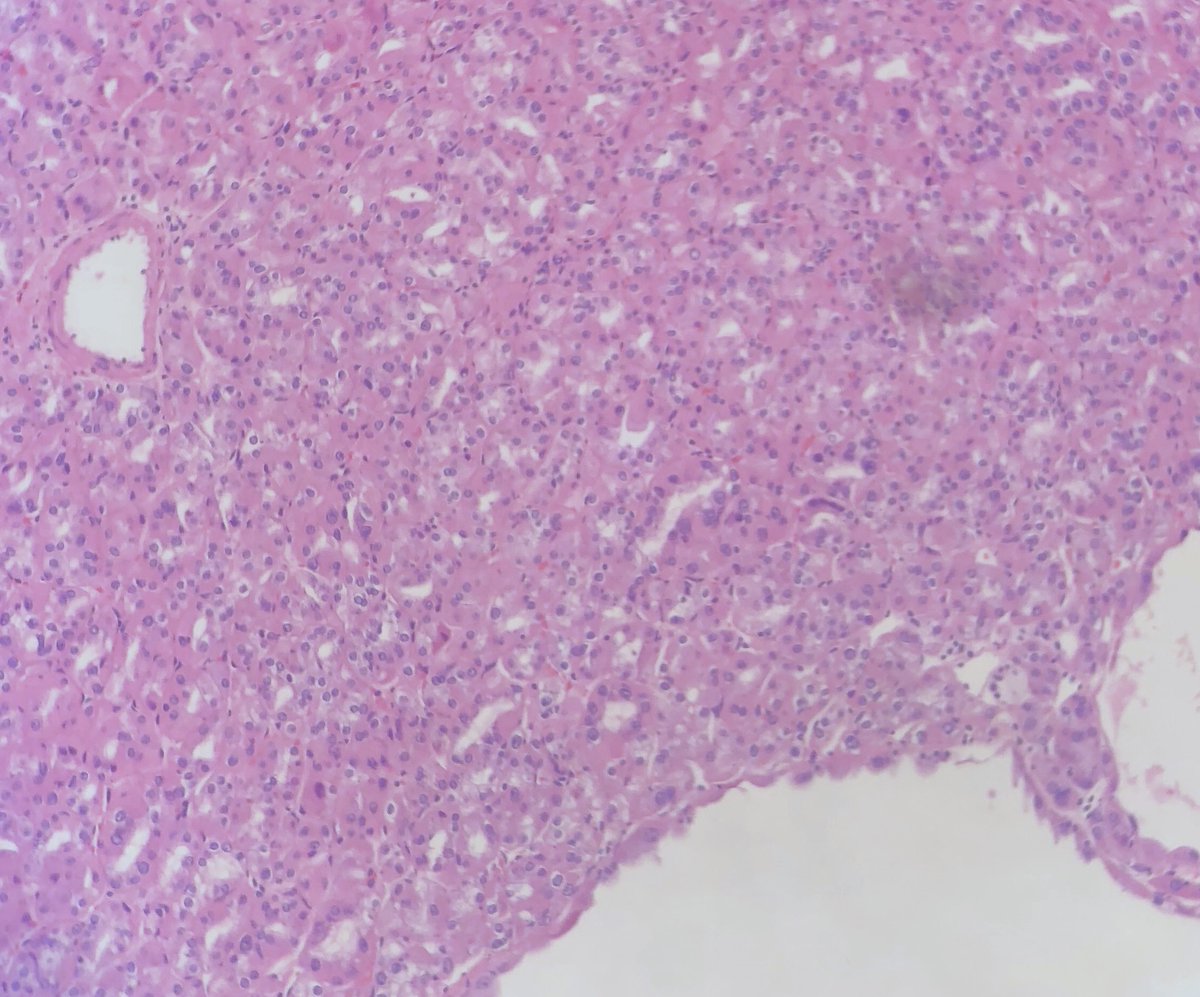

@StanfordPath Saturday!

65 YO man with a femur lesion. Had history of giant cell tumor of bone 20 years ago in same area. Patient treated with bisphos

Pleomorphic spindle cells in fascicles with necrosis. No giant cells

see IHC below

#stanfordpathsaturday#pathologytwitter pic.twitter.com/ZRmpS44FSt – mjesto: Stanford hospital